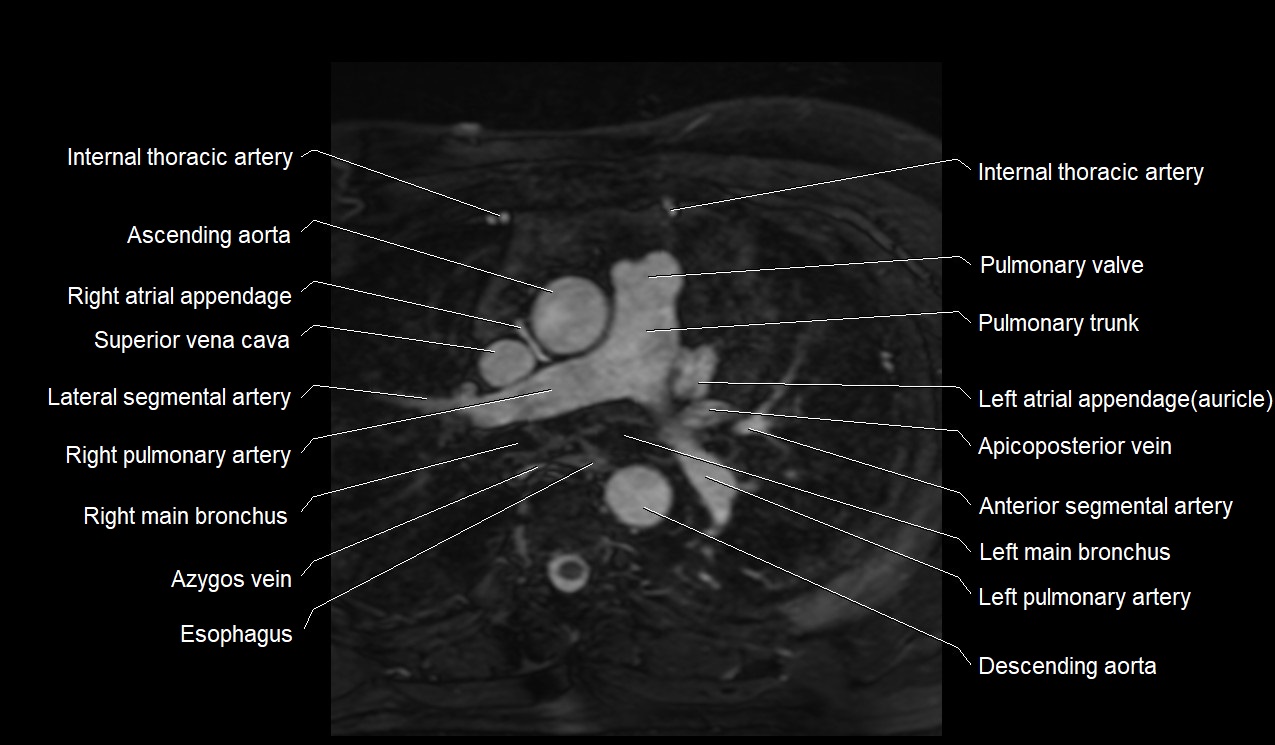

- Ascending aorta

- Azygos vein

- Left main bronchus

- Left pulmonary artery

- Pulmonary trunk

- Pulmonary valve

- Right pulmonary artery

- Superior vena cava